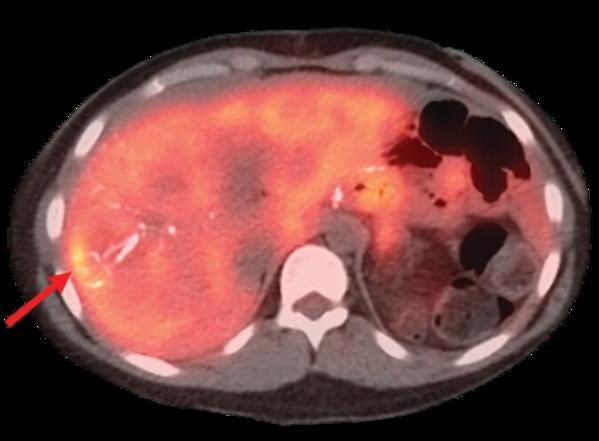

​Dr.Sasmita Vadgaonkar is the Best Surgical Oncologist in Mumbai, Oncologist in Mumbai, Oncosurgeon in Vile Parle,Mumbai. Dr.Sasmita Vadgaonkar is a highly skilled Consultant in Surgical Oncology with over 12 years of experience. Dr.Sasmita is specialized in advanced surgeries in Gastrointestinal, Hepatopancreatic biliary, Gynaecological, Urological, Cytoreductive surgeries, HIPEC, PIPAC, Head neck and Breast cancers. She has been trained in managing and treating complex Gastrointestinal, Hepato pancreatic biliary cancer cases, minimally invasive Laparoscopic and Robotic surgeries. She is certified for PIPAC under renowned experts Prof. Martin Hubner and Prof. Somshekhar at Aster Hospital, Bangalore and trained in CRS and HIPEC. Dr.Sasmita Vadgaonkar has completed her M.B.B.S and internship from MUHS (Maharashtra University of Health Science), Dr.VMGMC, Solapur before pursuing post graduation in General Surgery at Jehangir Hospital and Research Centre, Pune. There she refined her surgical skills and got trained in routine surgical cases and emergencies. Then she did her Doctorate in National Board of Surgical Oncology from Sir HN Reliance Foundation Hospital and Research centre where she got extensively trained in head neck cancers, Breast cancer, Gynaecological cancers, Soft tissue sarcoma, thoracic, Gastrointestinal and Hepato pancreatic biliary cancer surgeries. After the completion she did a 6 months post exclusively in the Breast Cancer unit at Sir HN Reliance Foundation Hospital and Research centre where she refined her skills in Breast surgeries, Oncoplasty and management of Breast Cancers. Then she got extensively trained in her primary focus of interest which is Gastrointestinal and Hepatopancreatic biliary cancer surgeries for 4years. She is an Intuitive certified Robotic Console Surgeon.